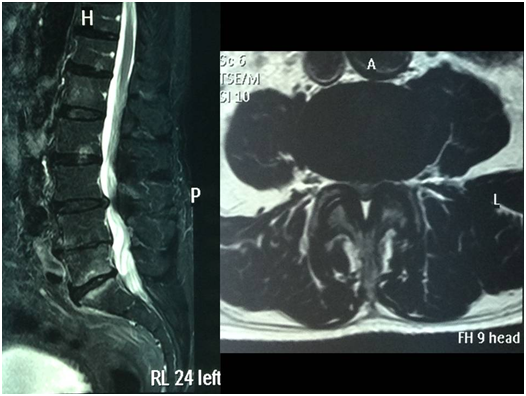

All the patients were assessed with dynamic lumbar X-rays and MRI of the lumbo-sacral spine. Patients with more than Grade II spondylolisthesis (Meyerding grading scale), mobile listhesis as shown in dynamic X-rays, spondylolysis, multisegmental narrow canals, facet synovial cysts and patients with a history of lumbar spine surgery were excluded. Thirteen male and seventeen female patients underwent surgery. Mean age was 66.7 yrs. (47-84); median age, 73. Levels L4-L5 (20), L3-L4 (6) y L5-S1 (4) were surgically managed (Figure 1).

Figure 1 case 1:  78 yrs old male presenting claudication at 50 meters. The MRI shows narrowing in the L3-L4 segment.  MED was performed and the clinical symptoms resolved.

Figure 4 Control MRI and CT scan of the patient in Figure 1.